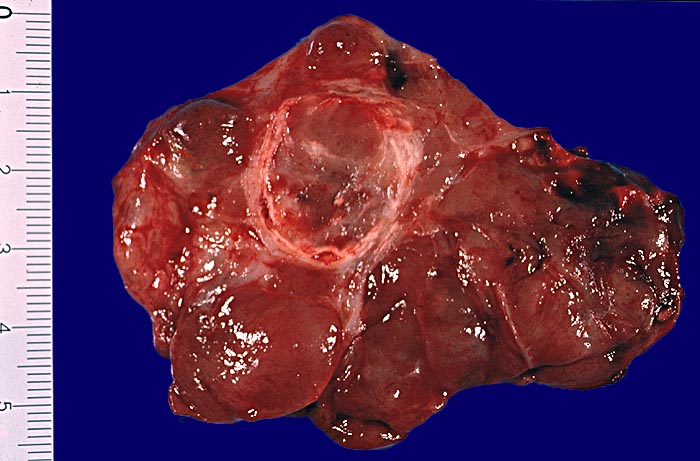

• Teils mikro- teils makrofollikuläre bekapselte Knoten.

• Tumorzellen ohne Kernatypien.

• Wenig Kolloid.

• Kapseldurchbrüche: Die breite bindegewebige Kapsel wird an mehreren Stellen pilzförmig vorgewölbt und an einigen Orten vollständig durchbrochen.

• Keine eindeutigen Gefässeinbrüche (keine Tumorthromben oder endothelialisierte Tumorzapfen in Venen der Kapsel oder jenseits der Kapsel). Das sollte der Kliniker dem Pathologen mitteilen: